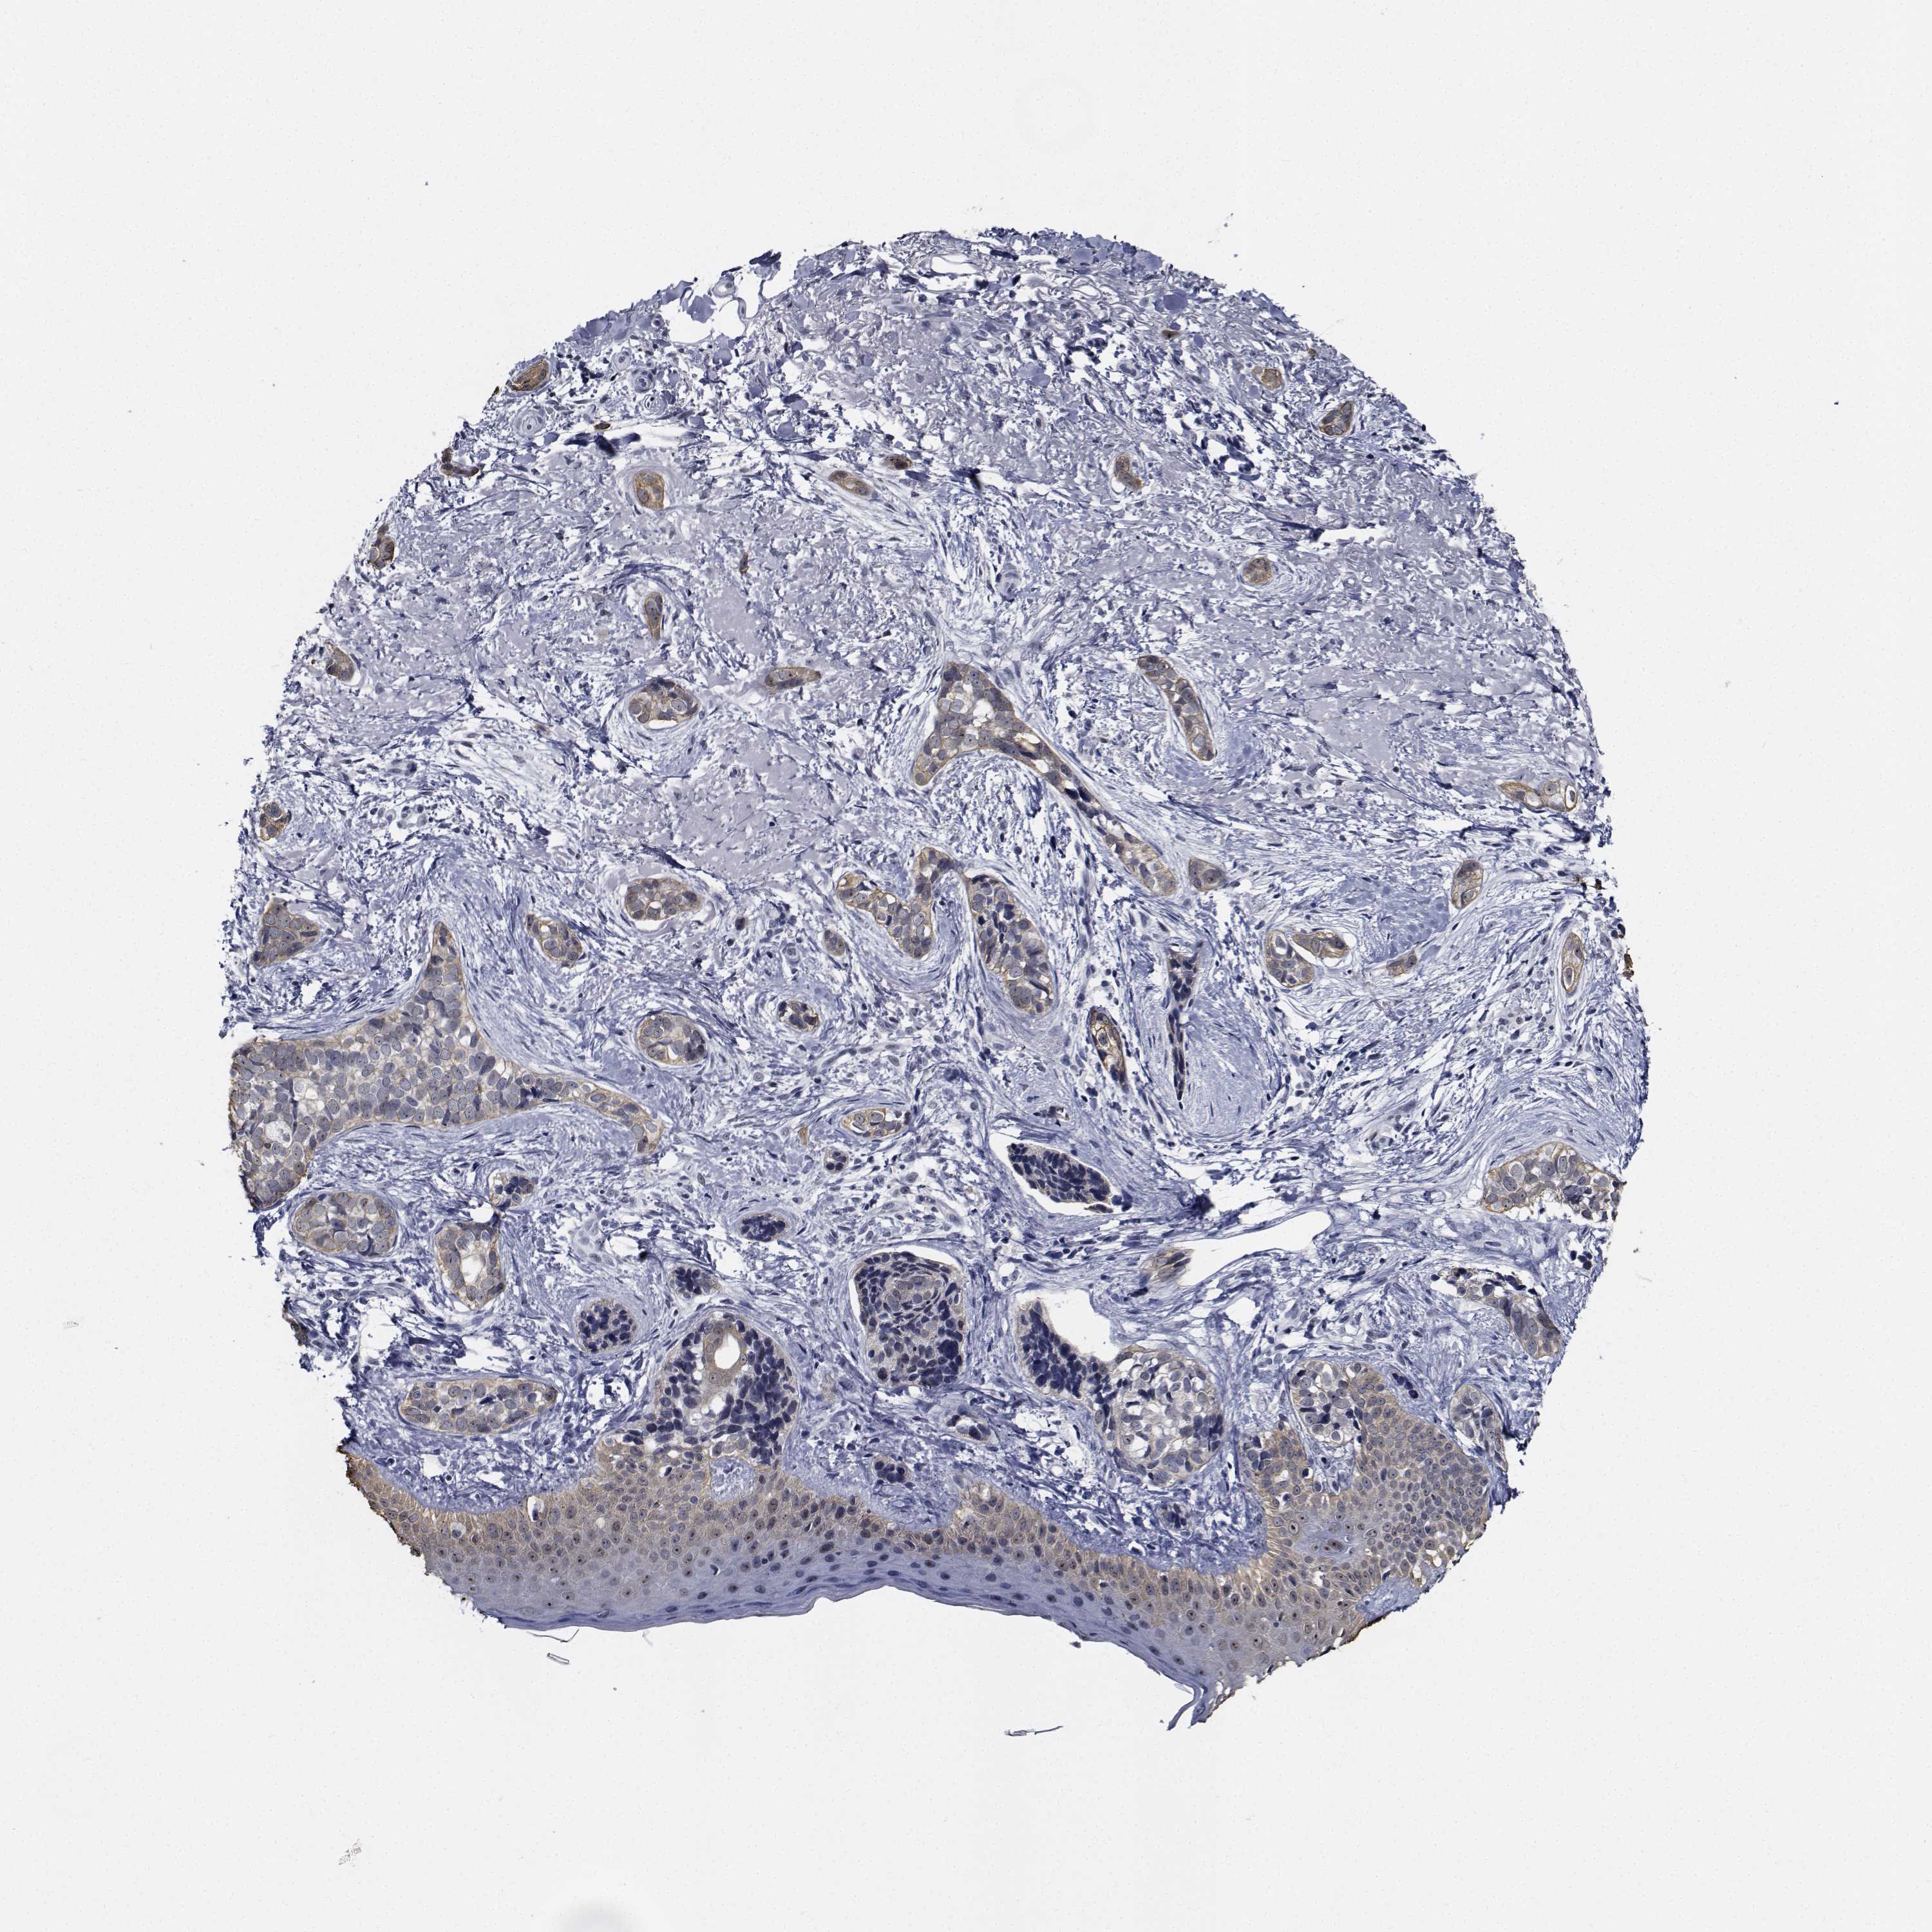

SKIN CANCER - Protein expressioni

A mouse-over function shows sample information and annotation data. Click on an image to view it in a full screen mode. Samples can be filtered based on level of antibody staining by selecting one or several of the following categories: high, medium, low and not detected. The assay and annotation is described here.

Each image is clickable and will lead to virtual microscopy that enables deeper exploration of all samples and also displays staining intensity scores, fraction scores and subcellular localization as well as patient and tissue information for each sample.

Antibody HPA028207

Antibody HPA028224

Antibody HPA028654

Staining

High

Medium

Low

Not detected

Intensity

Strong

Moderate

Weak

Negative

Quantity

>75%

75%-25%

<25%

None

Location

Nuclear

Cytoplasmic/membranous

Cytoplasmic/membranous,nuclear

Basal cell carcinoma

Squamous cell carcinoma, NOS